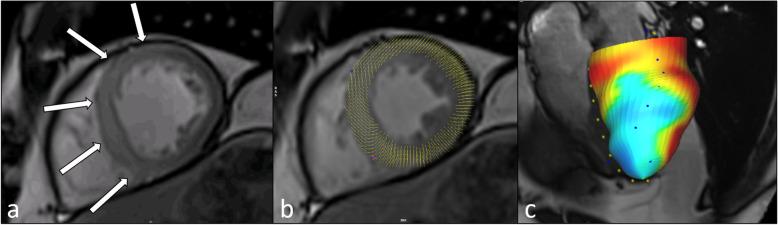

Ischemic heart disease and its sequelae are one of the major contributors to morbidity and mortality worldwide. Over the last decades, technological developments have strengthened the role of noninvasive imaging for detection, risk stratification, and management of patients with ischemic heart disease. Cardiac magnetic resonance (CMR) imaging incorporates both functional and morphological characterization of the heart to determine presence, acuteness, and severity of ischemic heart disease by evaluating myocardial wall motion and function, the presence and extent of myocardial edema, ischemia, and scarring. Currently established clinical protocols have already demonstrated their diagnostic and prognostic value. Nevertheless, there are emerging imaging technologies that provide additional information based on advanced quantification of imaging biomarkers and improved diagnostic accuracy, therefore potentially allowing reduction or avoidance of contrast and/or stressor agents. The aim of this review is to summarize the current state of the art of CMR imaging for ischemic heart disease and to provide insights into promising future developments.

缺血性心脏病及其后遗症是全球发病率和死亡率的主要原因之一。在过去的几十年中,技术的发展增强了无创成像在检测、风险分层和缺血性心脏病患者管理方面的作用。心脏磁共振(CMR)成像结合了心脏的功能和形态特征,通过评估心肌壁运动和功能、心肌水肿、缺血和瘢痕的存在和程度,来确定缺血性心脏病的存在、急性和严重程度。目前已建立的临床方案已经证明了其诊断和预后价值。然而,新兴的成像技术基于对成像生物标志物的高级定量和提高的诊断准确性提供了额外的信息,因此有可能减少或避免使用对比剂和/或应激剂。本综述的目的是总结 CMR 成像在缺血性心脏病中的最新技术,并探讨有前途的未来发展方向。